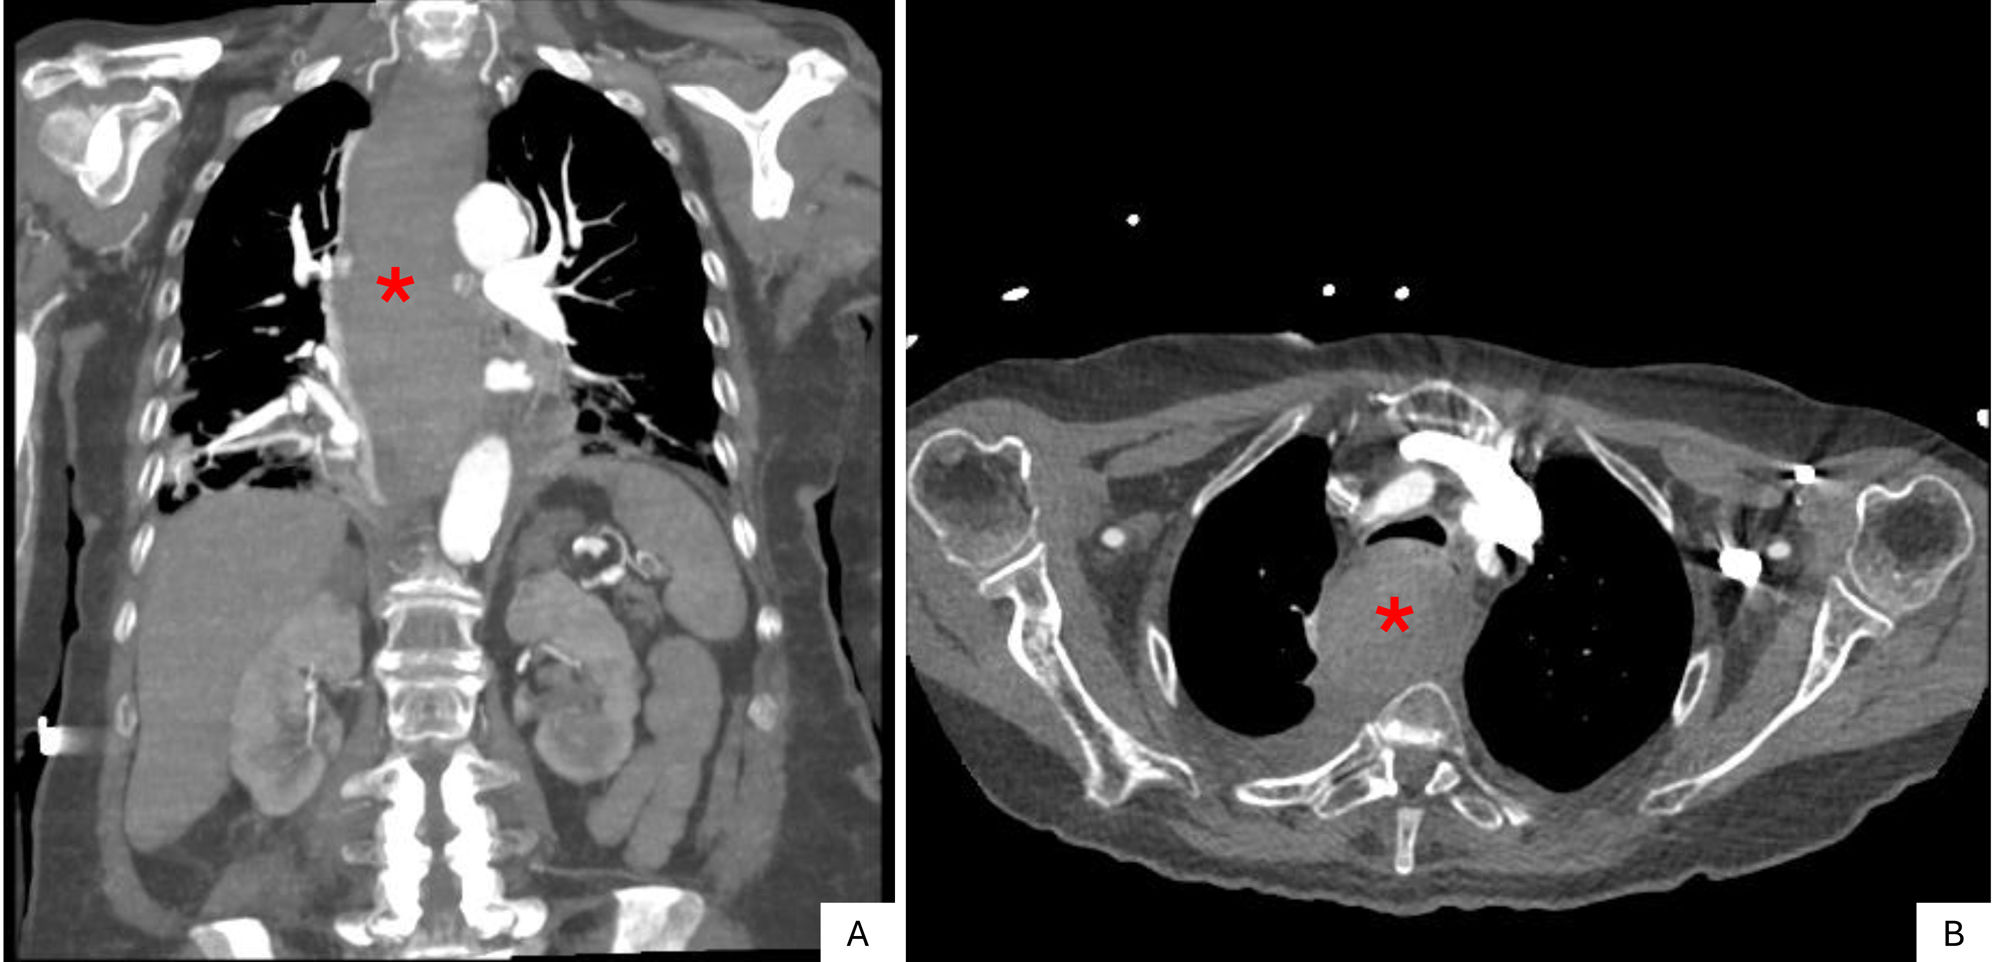

Intramural esophageal hematoma secondary to the spontaneous rupture of a parathyroid adenoma

Hematoma esofágico intramural secundario a la rotura espontánea de un adenoma paratiroideo